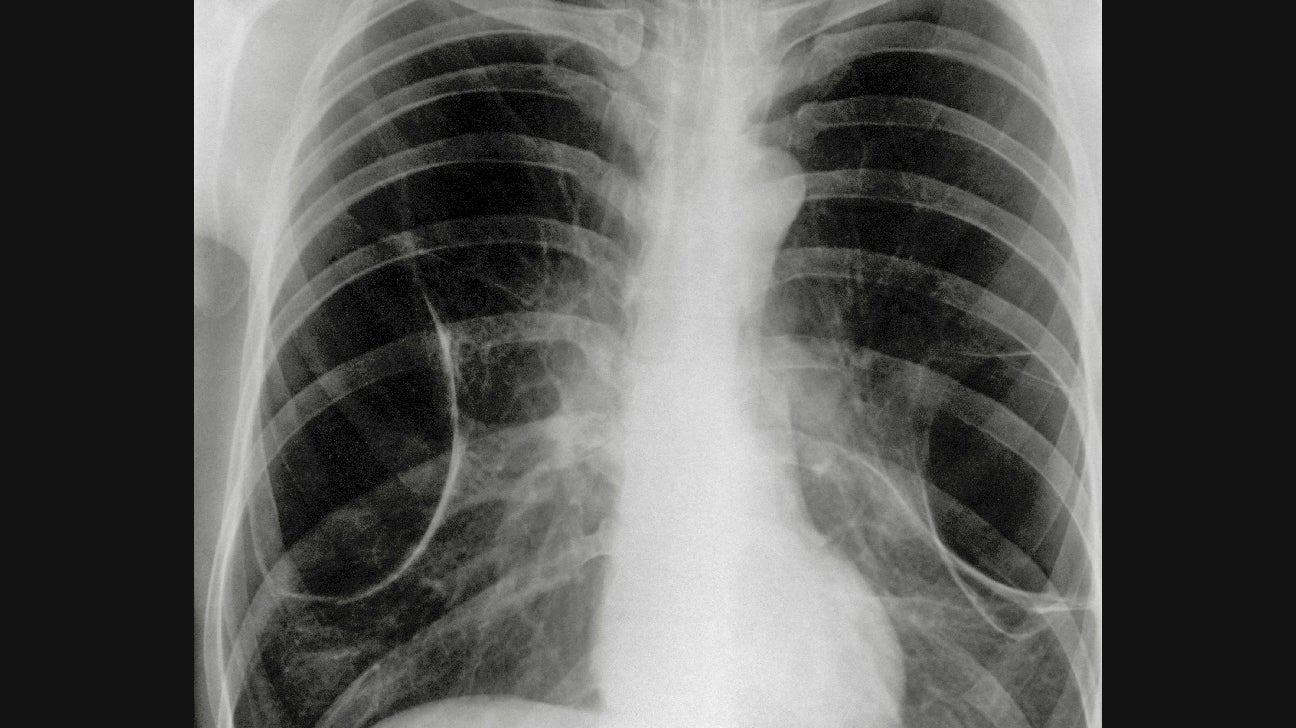

Web except in the case of very advanced disease with bulla formation, chest radiography does not image emphysema directly, but rather implies the. Web your healthcare provider may order the following tests to diagnose emphysema: They will also ask you about risk factors for emphysema, such as smoking,.

Emphysema Chest X Ray On A Chest X-Ray Emphysema Would Be Diagnosed By Web your healthcare provider may order the following tests to diagnose emphysema: Web except in the case of very advanced disease with bulla formation, chest radiography does not image emphysema directly, but rather implies the. They will also ask you about risk factors for emphysema, such as smoking,. On A Chest X-Ray Emphysema Would Be Diagnosed By.